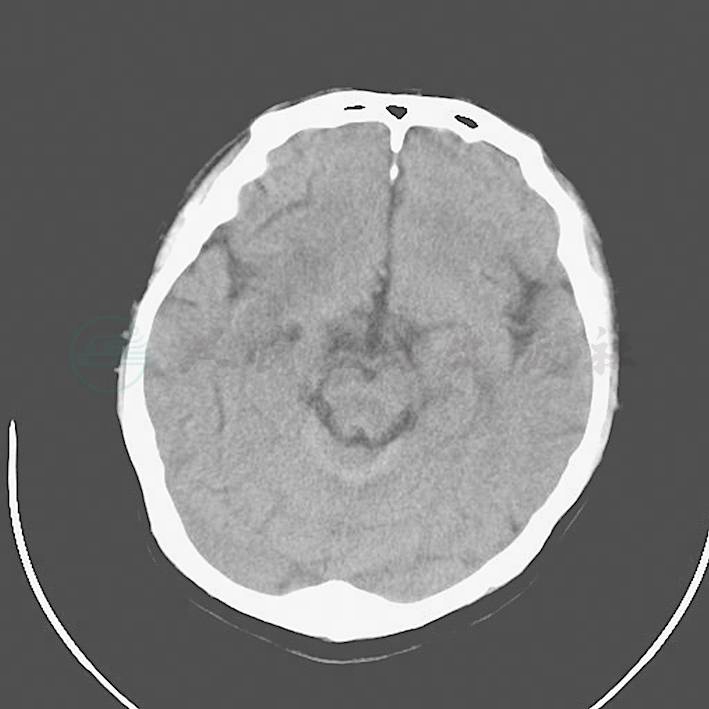

2.入院后考虑感染性心内膜炎,同时合并颅内脓肿、脾脓肿,反复送血培养,进一步明确病因的同时积极抗感染,方案为:万古霉素1g,每12小时1次结合头孢吡肟2g,每8小时1次。同时加用低分子肝素、前列地尔抗血栓、改善微循环治疗。患者入院后5日体温仍有升高,波动于38~39℃。有头痛,3月9日复查头颅CT(图1):右侧基底节区、侧脑室旁及左侧额顶叶大片状低密度影,梗死灶?感染?性质待定。查万古霉素血药浓度6.7μg/ml,低于有效浓度,更换为万古霉素0.5g,每6小时1次。

图1 右侧基底节区、侧脑室旁、双侧额顶叶及基底节区